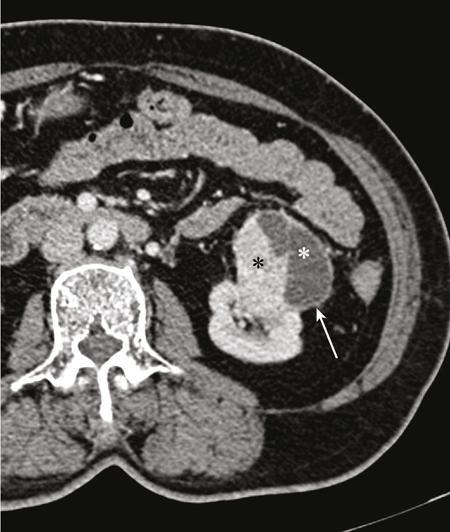

IMAGING OF RENAL MALIGNANCIES IN ADULTS Aparna Katdare, Palak Bhavesh Popat, Nilesh P. Sable, Ganesh Bakshi, Suyash Kulkarni Detection of renal masses has increased remarkably in recent times owing to wide-spread use of cross-sectional imaging. Imaging plays an important role in characterizing renal masses and is indispensable in treatment planning in renal malignancies. The most commonly encountered malignant renal masses in practice include renal cell carcinoma (RCC), urothelial carcinoma, lymphoma and metastases. Urothelial carcinoma and lymphoma have been covered in detail in separate chapters. RCC constitutes nearly 90% of all renal malignancies with a higher incidence in North America and Europe than India, Africa and China. With an increase in the number of cross-sectional studies performed, especially in Western population, the incidental diagnosis of RCC has increased in recent times, with such incidentally diagnosed lesions presenting at earlier stages with better prognosis and reduced rates of recurrence. The median age of presentation of RCC is 64 years according to the Surveillance, Epidemiology and End Results (SEER) program database and almost a decade earlier in Indian population, with a definite increasing risk of RCC with increasing age. Males are affected about 2–3.5 times more than females. In the Indian population, patients have been seen to present at a later stage as compared to the Western population. Amongst the various postulated risk factors, there is convincing evidence that smoking, hypertension, obesity and acquired renal cystic disease increase the risk of RCC. Alcohol intake and physical activity have been found to be associated with reduced risk of RCC. Trichloroethylene and cadmium exposure have been postulated as likely causes as well. Two to four per cent of RCCs are hereditary, with association of various genetic disorders such as Von Hippel Lindau (VHL) syndrome, hereditary papillary renal carcinoma, hereditary leiomyomatosis RCC, Birt-Hogg-Dube syndrome, chromosome 3 translocation and tuberous sclerosis (TCS1, TCS2). The WHO classification of 2016 (Table 11.25.1.1) stratifies tumours of the kidney into different subtypes based on cytoplasmic and architectural features, tumour location, background renal disease and molecular alterations. Clear cell renal cell carcinoma Multilocular cystic renal neoplasm of low malignant potential Papillary renal cell carcinoma Hereditary leiomyomatosis and renal cell carcinoma-associated renal cell carcinoma Chromophobe renal cell carcinoma Collecting duct carcinoma Renal medullary carcinoma MiT family translocation renal cell carcinomas Succinate dehydrogenase-deficient renal carcinoma Mucinous tubular and spindle cell carcinoma Tubulocystic renal cell carcinoma Acquired cystic disease-associated renal cell carcinoma Clear cell papillary renal cell carcinoma Renal cell carcinoma, unclassified Papillary adenoma Oncocytoma 8310/3 8316/1a 8260/3 8311/3* 8317/3 8319/3 8510/3a 8311/3a 8311/3 8480/3a 8316/3a 8316/3 8323/1 8312/3 8260/0 8290/0 Metanephric adenoma Metanephric adenofibroma Metanephric stromal tumour 8325/0 9013/0 8935/1 Nephrogenic rests Nephroblastoma Cystic partially differentiated nephroblastoma Paediatric cystic nephroma 8960/3 8959/1 8959/0 Clear cell sarcoma Rhabdoid tumour Congenital mesoblastic nephroma Ossifying renal tumour of infancy 8964/3 8963/3 8960/1 8967/0 Leiomyosarcoma Angiosarcoma Rhabdomyosarcoma Osteosarcoma Synovial sarcoma Ewing sarcoma Angiomyolipoma Epithelioid angiomyolipoma Leiomyoma Haemangioma Lymphangioma Haemangioblastoma Juxtaglomerular cell tumour Renomedullary interstitial cell tumour Schwannoma Solitary fibrous tumour 8890/3 9120/3 8900/3 9180/3 9040/3 9364/3 8860/0 8860/1a 8890/0 9120/0 9170/0 9161/1 8361/0 8966/0 9560/0 8815/1 Cystic nephroma Mixed epithelial and stromal tumour 8959/0 8959/0 Well-differentiated neuroendocrine tumour Large cell neuroendocrine carcinoma Small cell neuroendocrine carcinoma Phaeochromocytoma 8240/3 8013/3 8041/3 8700/0 Renal haematopoietic neoplasms Germ cell tumours The morphology codes are from the International Classification of Diseases for Oncology (ICD-O) {917A}, Behaviour is coded/0 for benign tumours; /1 for unspecified, borderline or uncertain behaviour; /2 for carcinoma in situ and grade III intraepithelial neoplasia; and /3 for malignant tumours. The classification is modified from the previous WHO classification (756A), taking into account changes in our understanding of these lesions. aNew code approved by the IARC/WHO Committee for ICD-O. Of these, the most common entity is the clear cell subtype, while papillary and chromophobe subtypes are less common. The different subtypes show varied biological behaviour, treatment response and prognosis. The 2017 guidelines by American Urological Association (AUA) as well as 2019 guidelines by European Society of Medical Oncology (ESMO) recommend multiphase cross-sectional imaging by either CT or MRI for renal mass characterization and staging. AUA 2017 guidelines recommend renal mass characterization on the basis of tumour complexity, contrast enhancement and presence or absence of fat. MRI has an upper hand over CT in characterizing subtle mass enhancement, cystic lesions and lesions less than 2 cm. ESMO recommends contrast-enhanced CT study of the chest, abdomen and pelvis for renal mass staging. Bone scan and brain CT or MRI can be considered if indicated by clinical or laboratory investigations. For characterization of renal masses, a multiphase CT or MRI study is recommended. CT study constitutes an unenhanced study followed by contrast injection and acquisition of corticomedullary phase at 40 seconds, nephrographic phase at around 100 seconds and delayed phase at around 5 minutes. MRI protocol includes T2-weighted single-shot fast spin-echo 2D sequences, axial T1-weighted 2D sequence with in-phase and opposed-phase gradient echo imaging, precontrast and postcontrast imaging with a 3D T1-weighted spoiled gradient recalled sequences in corticomedullary phase at 30 seconds, nephrographic phase at 100 seconds, 180–210 seconds and delayed phase imaging at 5 minutes and diffusion-weighted imaging with multiple b-values 0–50, 400–500 and 800–1000 s/mm2. The ACR White Paper on CT imaging of incidental renal mass recommends using the following descriptors for characterizing renal masses: Given the prognostic implications, it is worthwhile for radiologists to know the imaging features that may help discriminate between the common histological subtypes of RCC on various imaging modalities. This is the most common histological type of RCC, accounting for about 70% of cases. These are exophytic tumours with a heterogeneous appearance due to the presence of necrosis, intratumoural haemorrhage, cystic components with septations and calcific foci and hence have a more heterogeneous appearance on cross-sectional imaging than the other subtypes (Fig. 11.25.1.1). Necrosis is seen more often in larger masses and higher tumour grades (Fig. 11.25.1.2). On CT, depending on the tumour composition, these are seen as heterogeneous lesions, show marked contrast enhancement in the corticomedullary phase with washout on nephrogenic phase (Fig. 11.25.1.2). On MRI, these characteristically show high signal intensity on T2W sequences (Fig. 11.25.1.3). The presence of intracytoplasmic fat in the clear cells of the tumour is reflected in the loss of signal in opposed phase images on chemical shift imaging, which is seen in nearly 60% of these tumours. A pseudocapsule may be seen, which is best appreciated on T2-weighted imaging on MRI; the presence of a pseudocapsule has a high negative predictive value for perinephric extension (Figs. 11.25.1.3 and 11.25.1.4). Conversely, larger tumours with higher grades often have interrupted pseudocapsule and hence tend to be irregular, spread into the perinephric fat with renal vein and inferior vena cava (IVC) invasion (Figs. 11.25.1.5 and 11.25.1.6). On diffusion-weighted imaging, clear cell RCCs have been seen to have higher ADC values than nonclear cell RCCs, and lower-grade tumours have been seen to have higher ADC values than higher-grade tumours. The clear cell variant has worse prognosis than the papillary and chromophobe subtypes, presenting at a more advanced stage and being more likely to recur or metastasize (Fig. 11.25.1.7), with lower 5-year survival rates at 44%–69% as compared to 78%–92% for the other two. Papillary RCC comprises about 10%–15% of RCCs. These are slow-growing tumours and hence are well-marginated in contrast to clear cell RCC. As they are hypovascular, their enhancement on CT is significantly less than clear cell RCC (Fig. 11.25.1.8). These show characteristically low signal on T2W images on MRI (Fig. 11.25.1.9). Intracytoplasmic or macroscopic fat is less often seen on MRI imaging as compared to the clear cell variants. Larger tumours tend to be more heterogeneous (Fig. 11.25.1.10). These tumours may sometimes show cystic appearances, mural projections or blood degradation products. Calcifications are more common in papillary variants than clear cell RCC. Multifocality and bilaterality are also more common in these tumours than clear cell variants. These account for about 5% of RCCs. These are less aggressive, more homogeneous and hypovascular lesions than clear cell variants, with intensity of contrast enhancement on cross-sectional imaging being midway between clear cell and papillary variants. They show low to intermediate T2 signals on MRI. A characteristic feature is the presence of a central scar and spoke-wheel enhancement, the latter being a histopathological and imaging similarity between these tumours and oncocytoma (Fig. 11.25.1.11). Other subtypes of RCC are much less common but some may show distinct imaging findings. Multilocular cystic RCCs have excellent prognosis and lack mural nodules within the cystic components, unlike clear cell RCCs with cystic degeneration which show mural nodules. Collecting duct carcinomas, on the other hand, are aggressive tumours with poor prognosis and have medullary origin, and therefore appear similar to transitional cell carcinomas on imaging. Medullary RCCs are associated with sickle cell disease and sickle cell trait and are seen as infiltrating intracalyceal obstructive lesions with associated nodal disease. The imaging work-up of a suspected RCC is aimed at: Localized renal cancer is defined as a disease confined to the renal capsule and refers mainly to stage I and II disease. Nearly 70% of RCCs, especially the lower-stage lesions, are incidentally diagnosed on cross-sectional imaging. Also, amongst incidentally diagnosed renal lesions less than 4 cm in size, about 20% turn out to be benign on histopathology. Asymptomatic incidentally diagnosed small renal masses have an indolent course and better prognosis. Nephron-sparing surgery (NSS) has gathered momentum in recent years due to promising results and prognoses in small lesions. The 2017 AUA guidelines for localized renal masses describe restricted and well-defined indications for radical nephrectomy, bigger role of nephron-sparing procedures such as partial nephrectomy, tumour enucleation and thermal ablation, as well as increasing role for biopsy as well as active surveillance of such lesions. Hence, imaging findings in these lesions become critical in charting management of these patients. The imaging features of common histopathological subtypes of RCCs have already been discussed above. Signal intensity on T2W images and corticomedullary phase enhancement have been seen to be independent predictors of clear cell and papillary RCCs. Further, T2 signal homogeneity can be a predictor for slower growth rate. Hence, in general, multiparametric MRI studies have been shown to be effective in small renal mass characterization and can subsequently guide decisions regarding biopsy, surgery or surveillance. CT is a good alternative in patients with contraindication to MRI. For cystic renal lesions, the Bosniak classification, which stratifies the risk of neoplasia in cystic renal lesions based on the complexity of their appearance (wall thickness, septations, solid component), can be used effectively to decide further course of management. The Bosniak classification originally applies to CT findings but can logically be extrapolated to MRI, USG and Contrast Enhanced Ultrasound (CEUS) as well. Bosniak I and II cysts are benign while Bosniak IIF, III and IV cysts show progressively increasing risk of neoplasia. Given the more indolent course of cystic RCCs as compared to solid lesions and possible complications of interventions, lately there has been a case for even the type III and IV cysts, which previously would be operated, to be followed up, especially if patient has existing comorbidities or if the solid component is minimal. Initial follow-up would be at 6 months, followed by annual imaging. AUA 2017 guidelines recommend considering renal mass biopsy if haematologic, metastatic, inflammatory or infectious aetiology is suspected. Once the need for surgery is established in a localized disease, NSS may be considered for stage Ia and Ib disease. To predict perioperative outcomes in NSS, various scoring systems have been proposed for preoperative renal mass evaluation, such as R.E.N.A.L. nephrometry score, PADUA score (Preoperative aspects and dimensions used for anatomical classification), C-index method and mathematical tumour contact surface area (CSA). The popular R.E.N.A.L. nephrometry score takes into account various tumour descriptors that help decide the technical feasibility of NSS and predict surgical outcomes. These include tumour radius, exo/endophytic location, nearness to collecting system or renal sinus, anterior/posterior location and location with reference to polar lines. These descriptors need to be commented upon diligently while reporting renal masses (Table 11.25.1.4). Higher scores are seen to correlate with ischaemia time, postoperative urologic complications, higher grade and mortality. These include organ-confined tumours more than 7 cm in size, or tumours of any size which show regional nodal involvement and/or invasion of perinephric tissues but confined to Gerota’s fascia. These include renal vein and IVC invasion (luminal and mural). Generally, radical nephrectomy is recommended by the National Comprehensive Cancer Network (NCCN) in stage II and III RCCs. Both CT and MRI are effective in diagnosing locally advanced disease in RCC. The loss or interruption of pseudocapsule is seen in more infiltrative and aggressive disease and is best seen on MRI. Local infiltration may be in the form of contiguous spread to perinephric tissues or discrete deposits in perinephric fat (Fig. 11.25.1.15). IVC or renal vein invasion could be in the form of intraluminal thrombosis or invasion of the vessel wall and have implications on surgical approach and outcomes. Tumour thrombus can be distinguished from bland thrombus by confirming vascularity within the thrombus on imaging. Doppler evaluation, CEUS, CT and MRI can all be helpful for the same. MRI is better than other modalities for venous evaluation, especially for mural invasion and IVC invasion (Figs. 11.25.1.16 and 11.25.1.17). Right-sided tumours, anteroposterior IVC diameter of 2.4 cm or more at the level of renal hilum and complete IVC occlusion at this level are associated with higher risk of IVC resection. About 16% of patients with RCC have metastases at diagnosis and about 20%–30% of patients operated for local disease develop recurrence or metastases at a later date. The recurrent disease occurs most commonly within 3 years of diagnosis and uncommonly even later in young patients or large tumours. The most common sites of metastases from RCC are lungs, liver, bones, nodes, adrenals and brain. CT scan is the preferred modality for primary staging and surveillance for metastases because of its widespread availability and versatility for diagnosing bone and soft tissue lesions. MRI is preferred for looking for recurrence in postablative lesions, wherein these are seen as new enhancing lesions or show increase in the size of preexisting enhancing components. 18FFluorodeoxyglucose – Positron Emission Tomography (PET)/CT and PET/MRI may be helpful to look for metastatic disease as well. 18FSodium fluoride – PET/CT has been found to be better than CT and bone scan in detecting osseous metastases. RCC is a relatively radiation-resistant tumour, and treatment options tilt in favour of surgical procedures for localized and locally advanced diseases. For metastatic disease, post-risk assignment, the treatment has to be planned. Treatment can be offered as per size and the clinical stage.